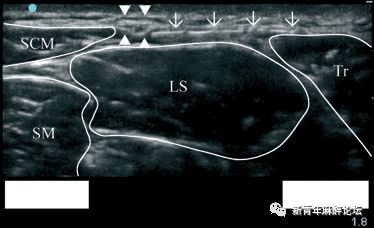

(注:超声引导副神经阻滞图像,SCM:胸锁乳突肌;LS:肩胛提肌;TR:斜方肌;SM:中斜角肌。关注图片深度为1.8cm,四个三角所指为副神经)